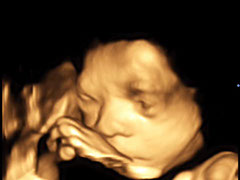

Hier zeigt ein kleiner Film einen 4D-Ultraschall

Klicken, um den Film zu sehen

Baby 4D UltraschallBaby 4D UltraschallBaby 4D UltraschallBaby 4D UltraschallBaby 4D UltraschallBaby 4D UltraschallBaby 4D UltraschallBaby 4D UltraschallBaby 4D UltraschallBaby 4D UltraschallBaby 4D UltraschallBaby 4D Ultraschall4 - 6<>